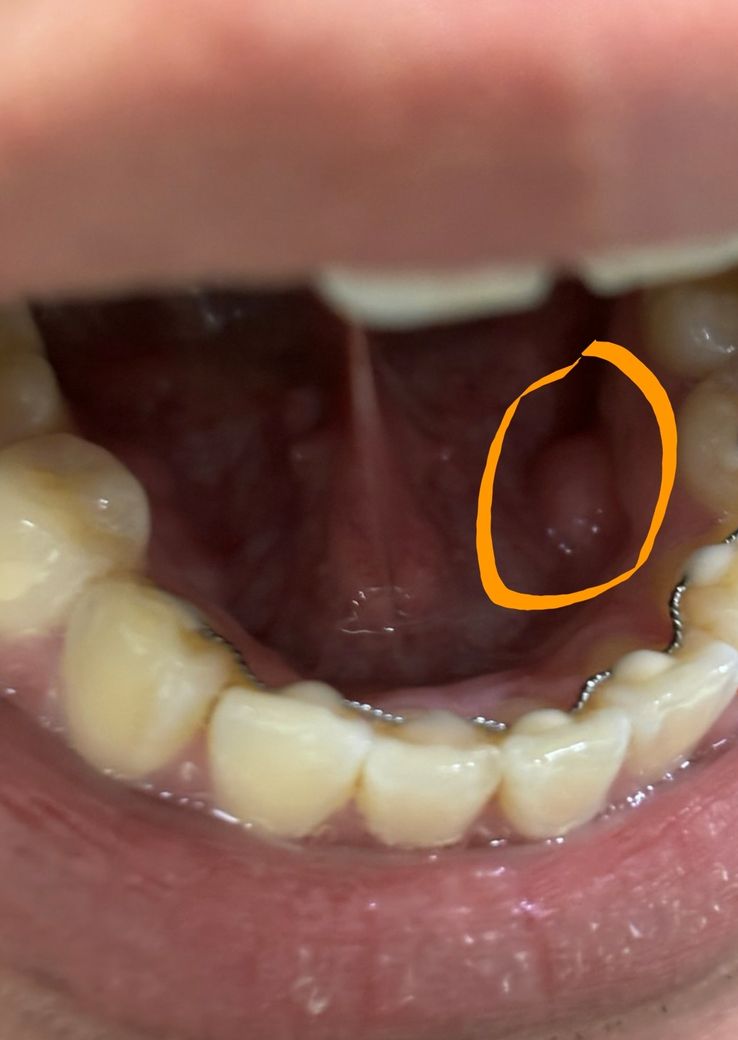

아래 잇몸 안쪽에 딱딱한 큰 뼈 같은게 뭔가요?

오래전부터 있었고 치과에서는 한번도 언급한적은없습니다.

그래서 큰 문제는 아닐것같긴하지만 남들에겐 없어보여서 궁금합니다. 저게 뭔가요? 딱딱해요.

사진에 보이는 부분은 잇몸뼈가 튀어 나온거입니다. 개인마다 차이가 잇는걸로 크게 문제가 되는건 아닙니다.

하악골 융기라고 하는 뼈가 있습니다. 남들도 가지고 있는 사람도 많으며 치료하지 않아도 됩니다.

딱딱하다고 하였으니 뼈가 돌출된 것으로 골융기(torus)라고 합니다. 조금씩 자랄수도 있지만 그냥 두면 됩니다.

해당 부위는 외골증으로 인해서 뼈가 안쪽으로 자라나온 것입니다.

크게 문제를 발생시키는 것은 아니기 때문에 걱정하지 않으셔도 되나 너무 딱딱한 음식을 먹게 되면 해당 부위에 상처가 발생할 수 있기 때문에 딱딱한 음식을 먹는 것을 줄이는 것이 좋습니다.